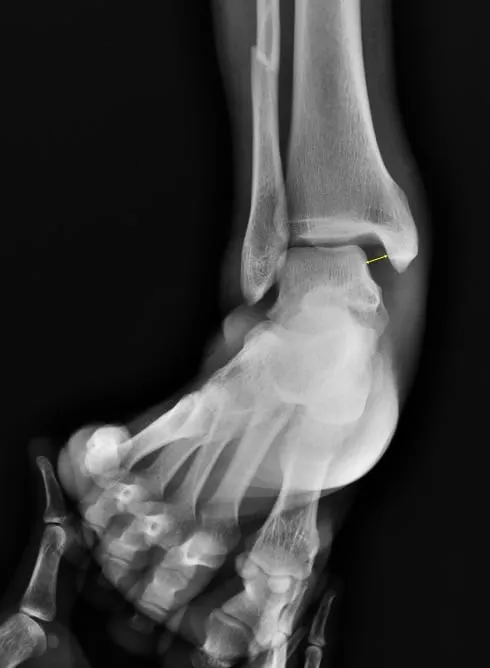

Stress view

The Stress View of the Ankle is a specialized radiographic technique used to evaluate the stability of the ankle ligaments, particularly following sprains or suspected ligament injuries. During this procedure, the ankle is imaged while a controlled force is applied to stress the joint—either by inverting or everting the foot—to test the integrity of the lateral or medial ligaments, respectively. This allows for clear visualization of any abnormal widening of the joint space or tilting of the talus, which may indicate ligament rupture or instability. The stress view is especially useful for assessing injuries to the anterior talofibular ligament (ATFL) or the deltoid ligament and plays a crucial role in diagnosing chronic ankle instability and planning appropriate treatment.